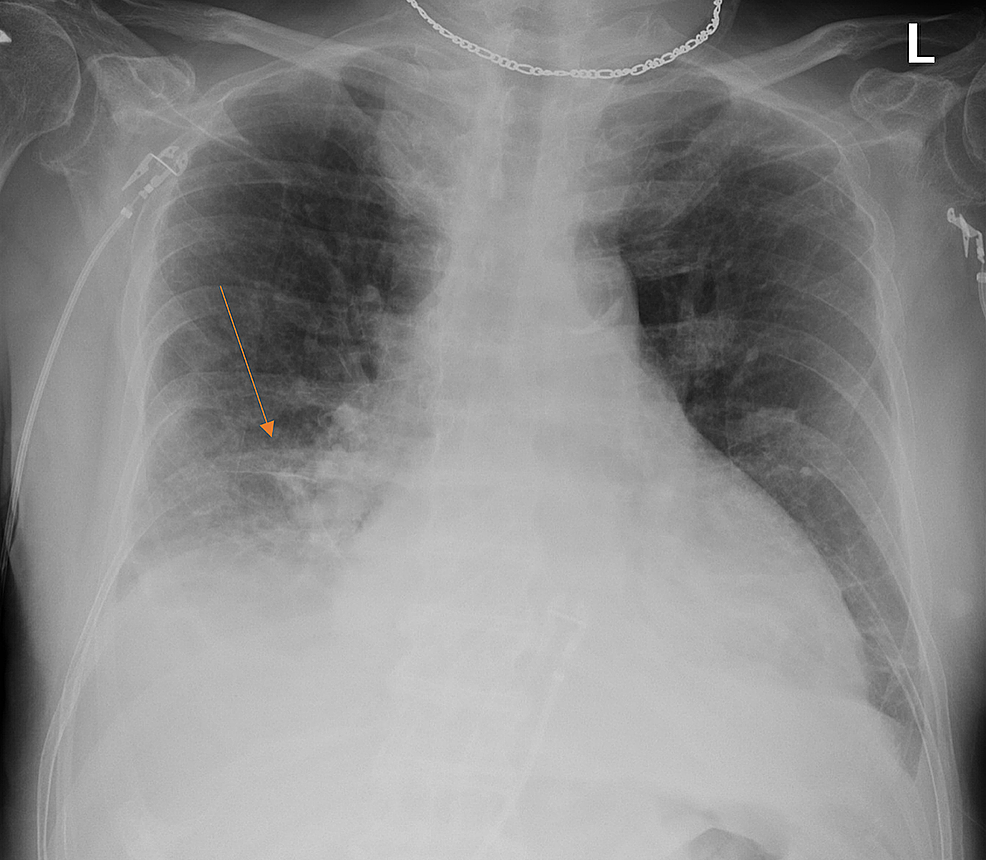

Linear Atelectasis around the Hilum on Chest Radiography A Novel Sign

Chest Xray showing the right basilar subsegmental atelectasis (arrow Linear Atelectasis On Chest X Ray In most cases affecting adults, atelectasis will appear in the lower left lobe of the lungs. The underlying cause (such as. This simple test uses a small device. Treatment includes maintaining coughing and deep breathing and treating the cause. Your healthcare provider may use a computed tomography (ct) scan to get more detailed pictures if. Atelectasis, characterized by the partial. Linear Atelectasis On Chest X Ray.